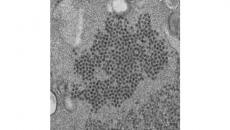

When the body encounters a new germ, it makes proteins called antibodies that are specially targeted to fight that particular infection. The antibodies float in plasma — the yellowish, liquid part of blood. Because it takes a few weeks for antibodies to form, the hope is that transfusing someone else’s antibodies could help patients fight the virus before their own immune system kicks in.